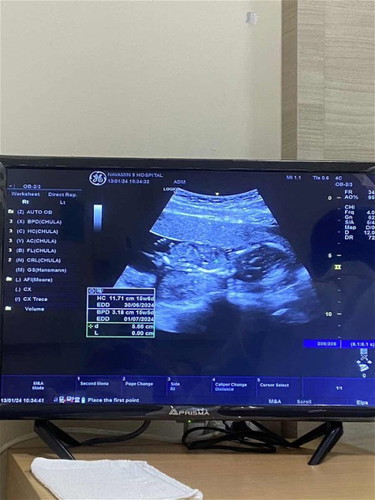

สอบถามค่ะแม่ๆตอนนี้16wแต่หมอบอกยังไม่ทราบเพศน้องแปลว่าน้องหนีบไว้ใช่ไหมคะแม่เห็นเพศกันกี่wคะ ซาว์หน้าท้อง

รูปอัลตราซาวล่าสุดค่ะ#ท้องแรกคะ